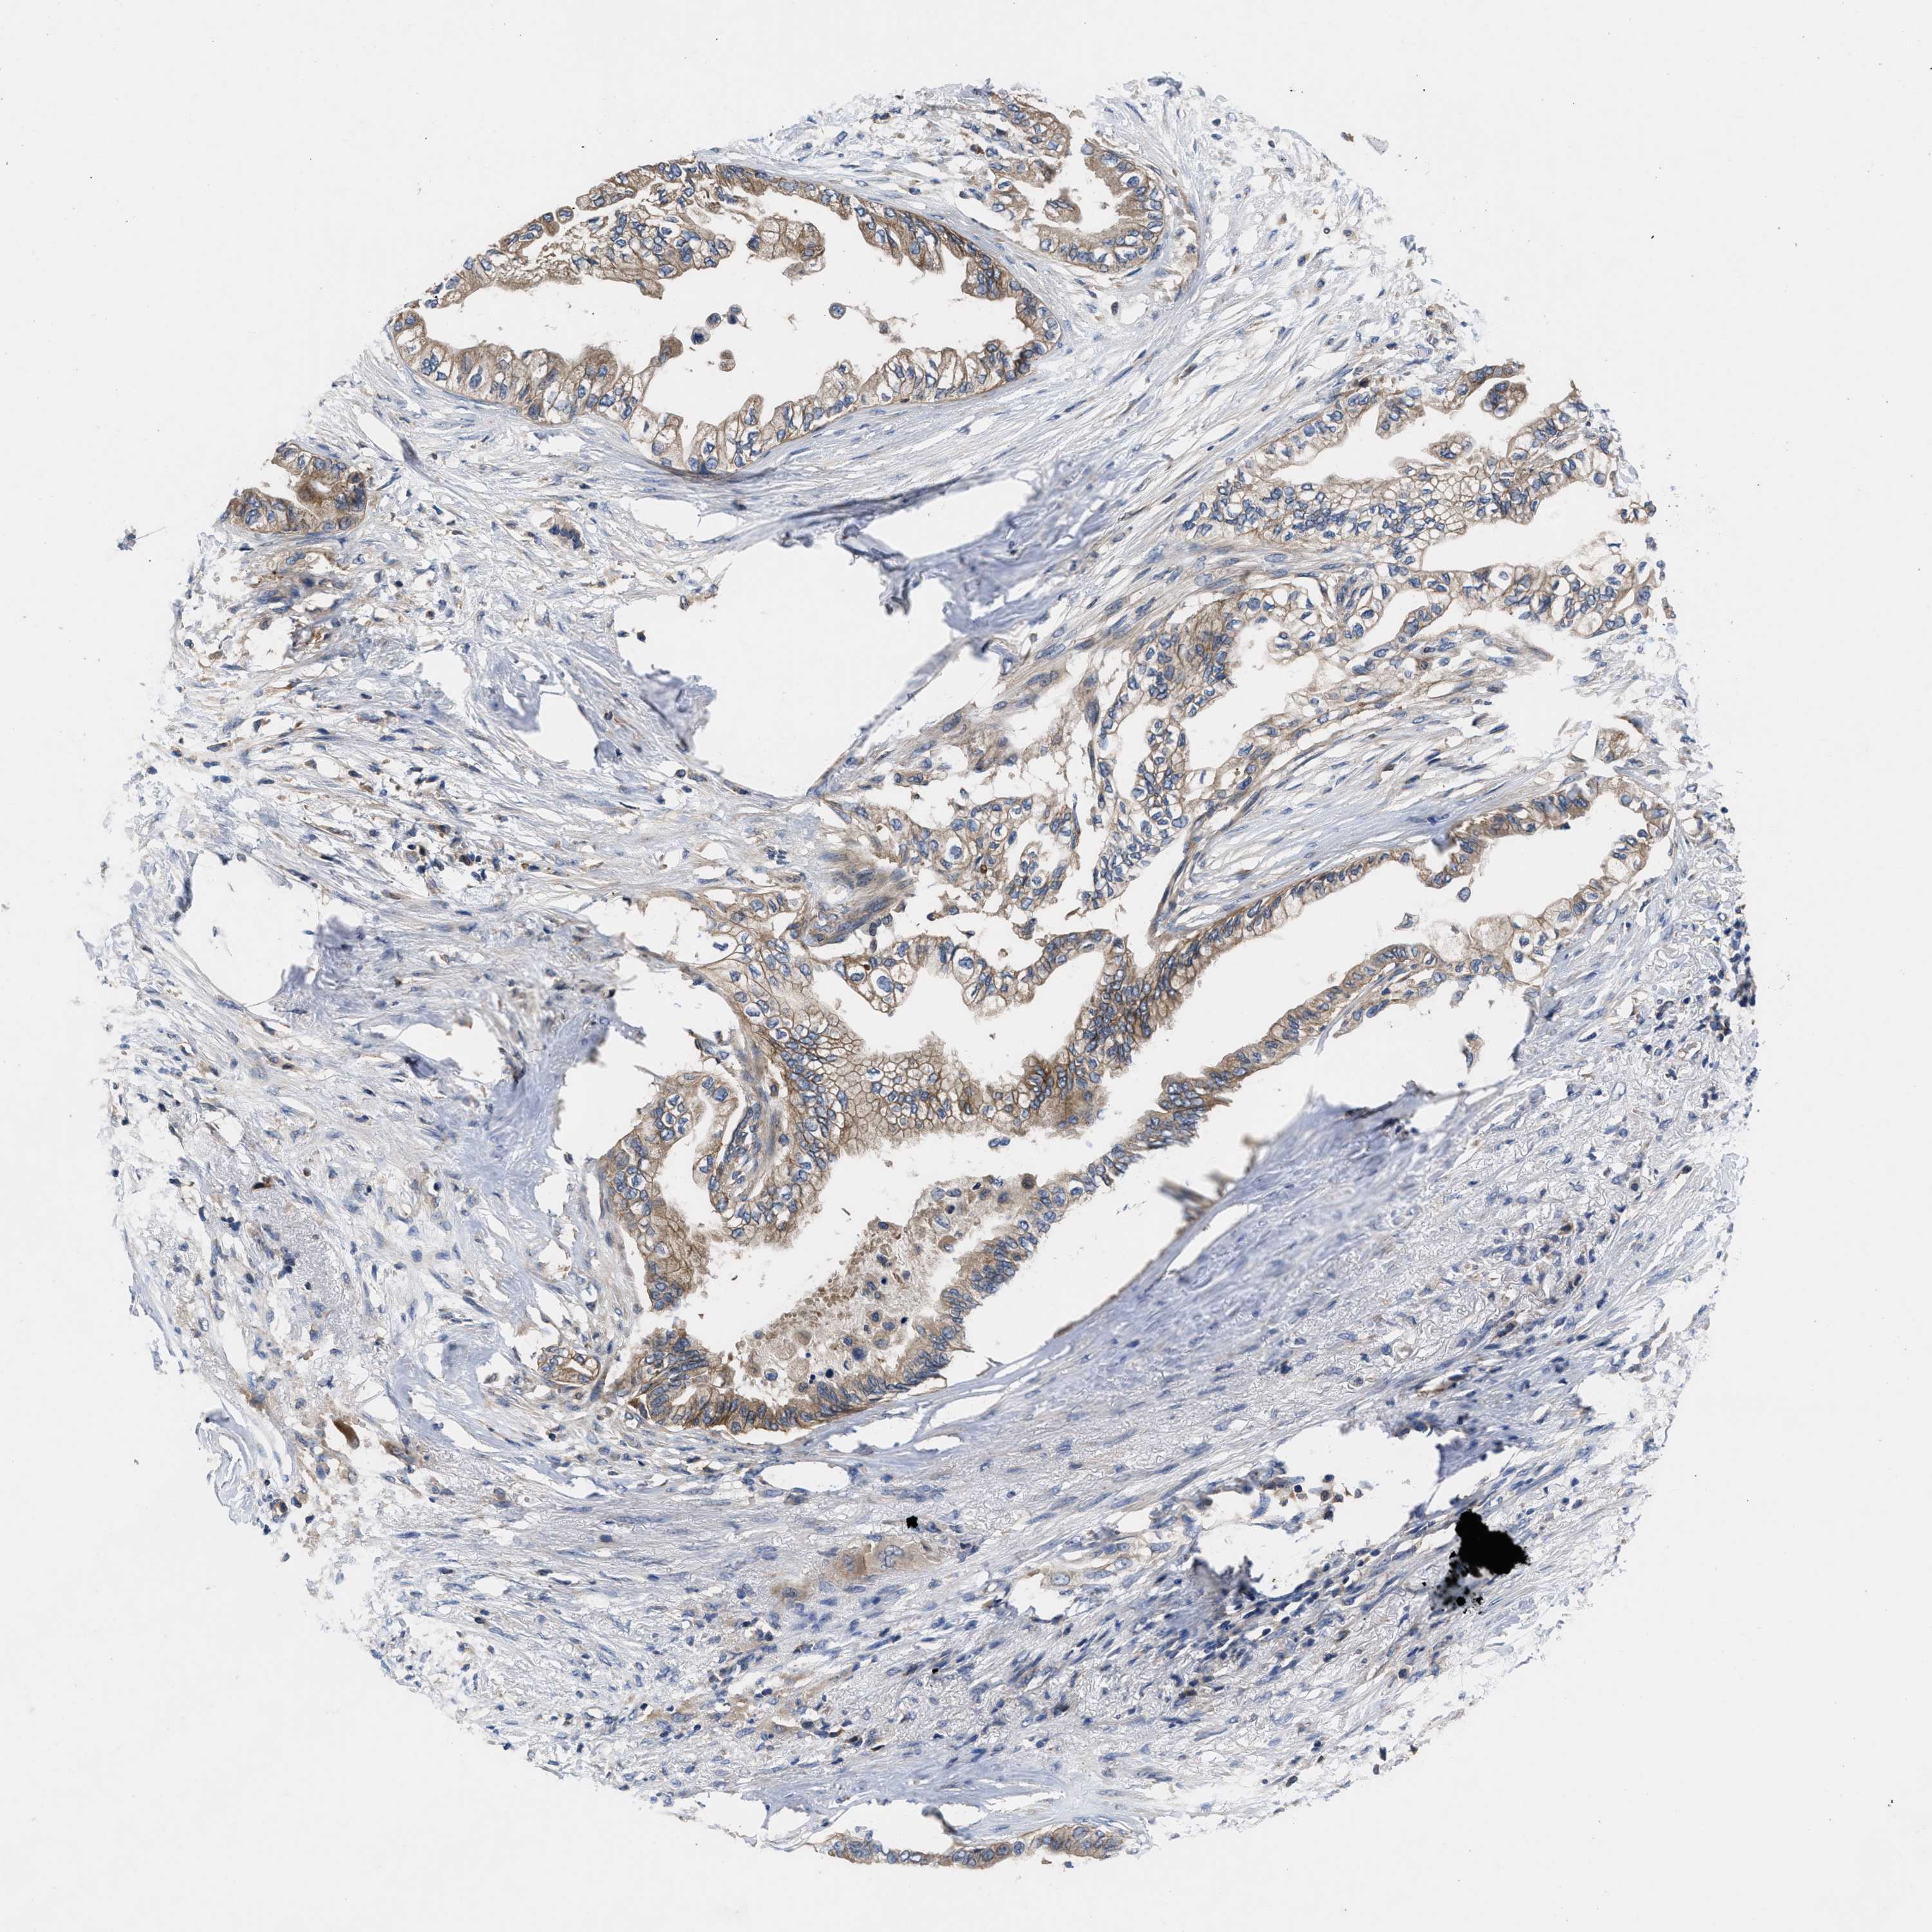

PANCREATIC CANCER - Protein expressioni

A mouse-over function shows sample information and annotation data. Click on an image to view it in a full screen mode. Samples can be filtered based on level of antibody staining by selecting one or several of the following categories: high, medium, low and not detected. The assay and annotation is described here.

Note that samples used for immunohistochemistry by the Human Protein Atlas do not correspond to samples in the TCGA dataset.

Antibody stainingi

Antibody staining in the annotated cell types in the current human tissue is reported as not detected, low, medium, or high, based on conventional immunohistochemistry profiling in selected tissues. This score is based on the combination of the staining intensity and fraction of stained cells.

Each image is clickable and will lead to virtual microscopy that enables deeper exploration of all samples and also displays staining intensity scores, fraction scores and subcellular localization as well as patient and tissue information for each sample.

Antibody HPA018162

Staining

High

Medium

Low

Not detected

Intensity

Strong

Moderate

Weak

Negative

Quantity

>75%

75%-25%

<25%

None

Location

Nuclear

Cytoplasmic/membranous

Cytoplasmic/membranous,nuclear

Adenocarcinoma, NOS